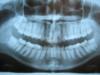

LilyAnn Опубликовано 20 апреля, 2007 Автор Поделиться Опубликовано 20 апреля, 2007 Вот ТРГ и ОРПГ. Надеюсь, после манипуляций со сканированием что-нибудь видно...Буду рада любой информации (записям из ординатуры особенно ) ТРГ и ОРПГ ниже... Ссылка на комментарий

LilyAnn Опубликовано 21 апреля, 2007 Автор Поделиться Опубликовано 21 апреля, 2007 Вот ТРГ! Сделала все, как сказали надеюсь, получилось лучше... Ссылка на комментарий

Bier Опубликовано 21 апреля, 2007 Поделиться Опубликовано 21 апреля, 2007 Вот ТРГ! Сделала все, как сказали надеюсь, получилось лучше... значительно лучше, еще бы и ОПТГ также и не боком Ссылка на комментарий

LilyAnn Опубликовано 22 апреля, 2007 Автор Поделиться Опубликовано 22 апреля, 2007 значительно лучше, еще бы и ОПТГ также и не боком ... и не боком Ссылка на комментарий

Doc Опубликовано 22 апреля, 2007 Поделиться Опубликовано 22 апреля, 2007 ... и не боком Не боком. Но все равно не видно. Закачать не успели видать. Ссылка на комментарий

Doc Опубликовано 22 апреля, 2007 Поделиться Опубликовано 22 апреля, 2007 да, действительно, что-то файл не закачивался... ФОтоаппарат плохо сфокусировался. Но ортодонты, они и так все разглядят! Ссылка на комментарий